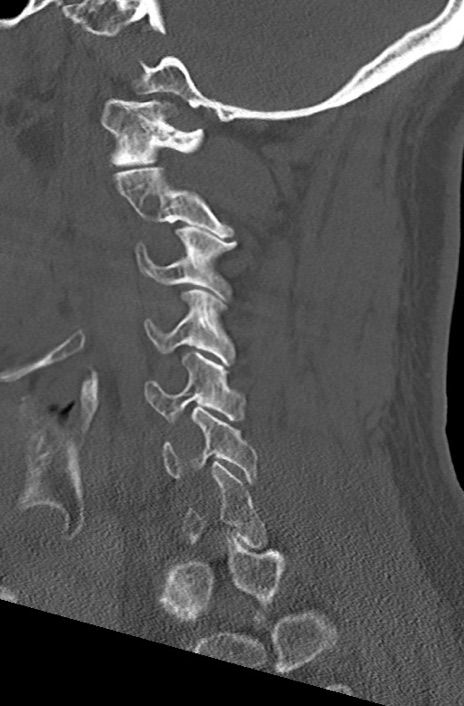

頚椎CT

矢状断像と横断像